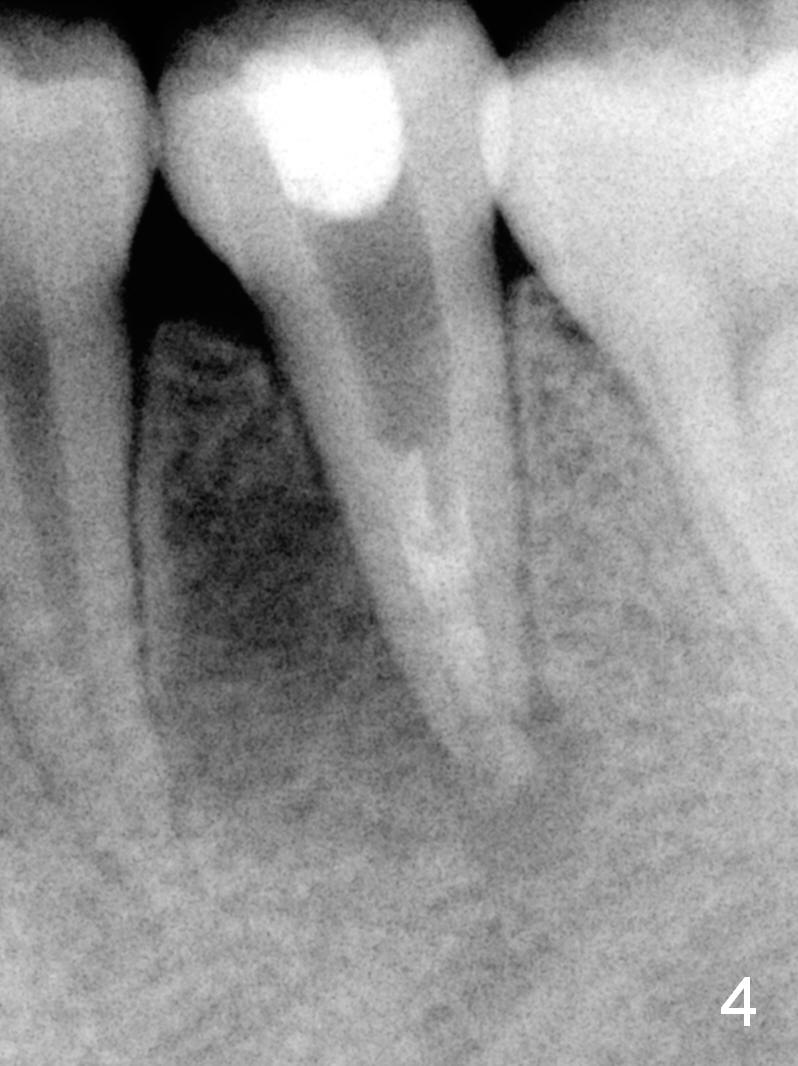

A 13-year-old girl has a buccal apical fistula at the tooth #20 with large periradicular radiolucency (Fig.1 *). After canal debridement, calcium hydroxide paste is placed in the canal (Fig.2 *). One month later, the fistula does not disappear with light percussion. New paste is placed (Fig.3). Two months later, the fistula disappears without percussion. The existing paste (Fig.4) is changed (Fig.5 (yellow: radiolucency; red: Inferior Alveolar Canal)). Another 2 months later, the fistula does not recur; as before, the paste density decreases, so does periradicular radiolucency (Fig.6). Root canal is packed (Fig.7). Six months postop, periradicular radiolucency continues to decrease, while the lamina dura at the apex is discontinuous (Fig.8 between arrowheads). Seven years postop, the lamina dura at the apex is seemingly intact (Fig.9). The patient remains asymptomatic at #20. In fact there is an acute infection at #29.